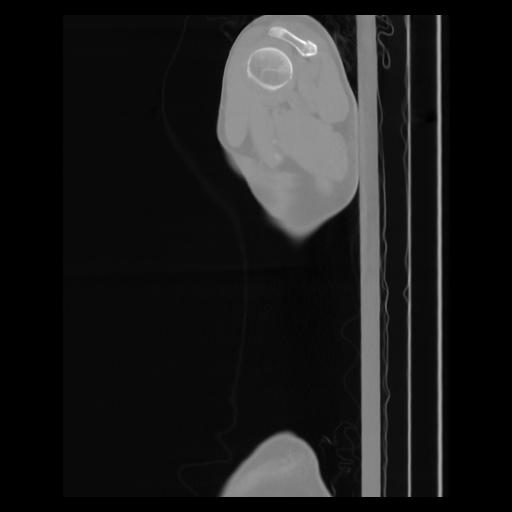

30 CUERPO,CE,Sagittal,3.000,CUERPO,Sagittal,